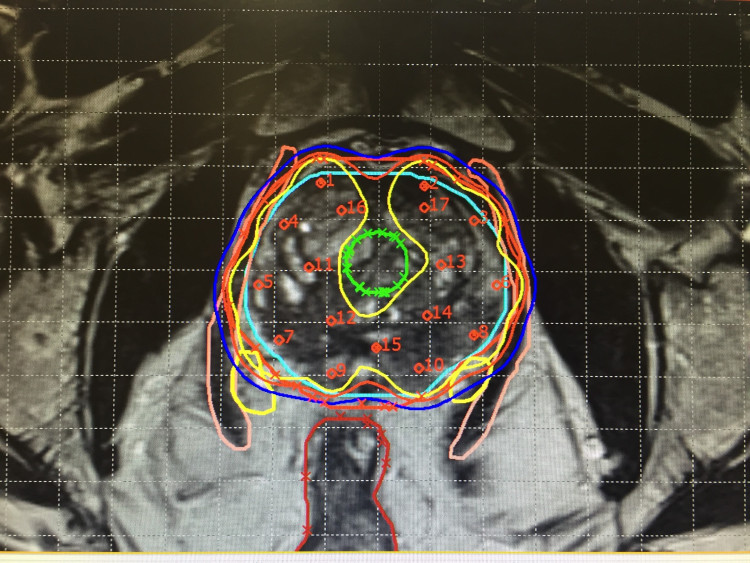

治疗规划,医学成像可用于治疗规划:从药物治疗和放射治疗到手术或者在某些情况下的姑息治疗。在放射治疗规划时,医学成像能生成肿瘤的三维图像,使放射治疗对肿瘤的靶向性更好,同时尽量减少对健康组织的伤害。

图像引导放射治疗是在放射治疗过程中纳入了实时医学成像,以确保辐射剂量准确且均匀。

详尽的医学图像有助于医疗卫生专业人员区分肿瘤、健康组织和器官,以确保准确地以癌细胞为靶向。(照片来源:Auna Oncosalud)